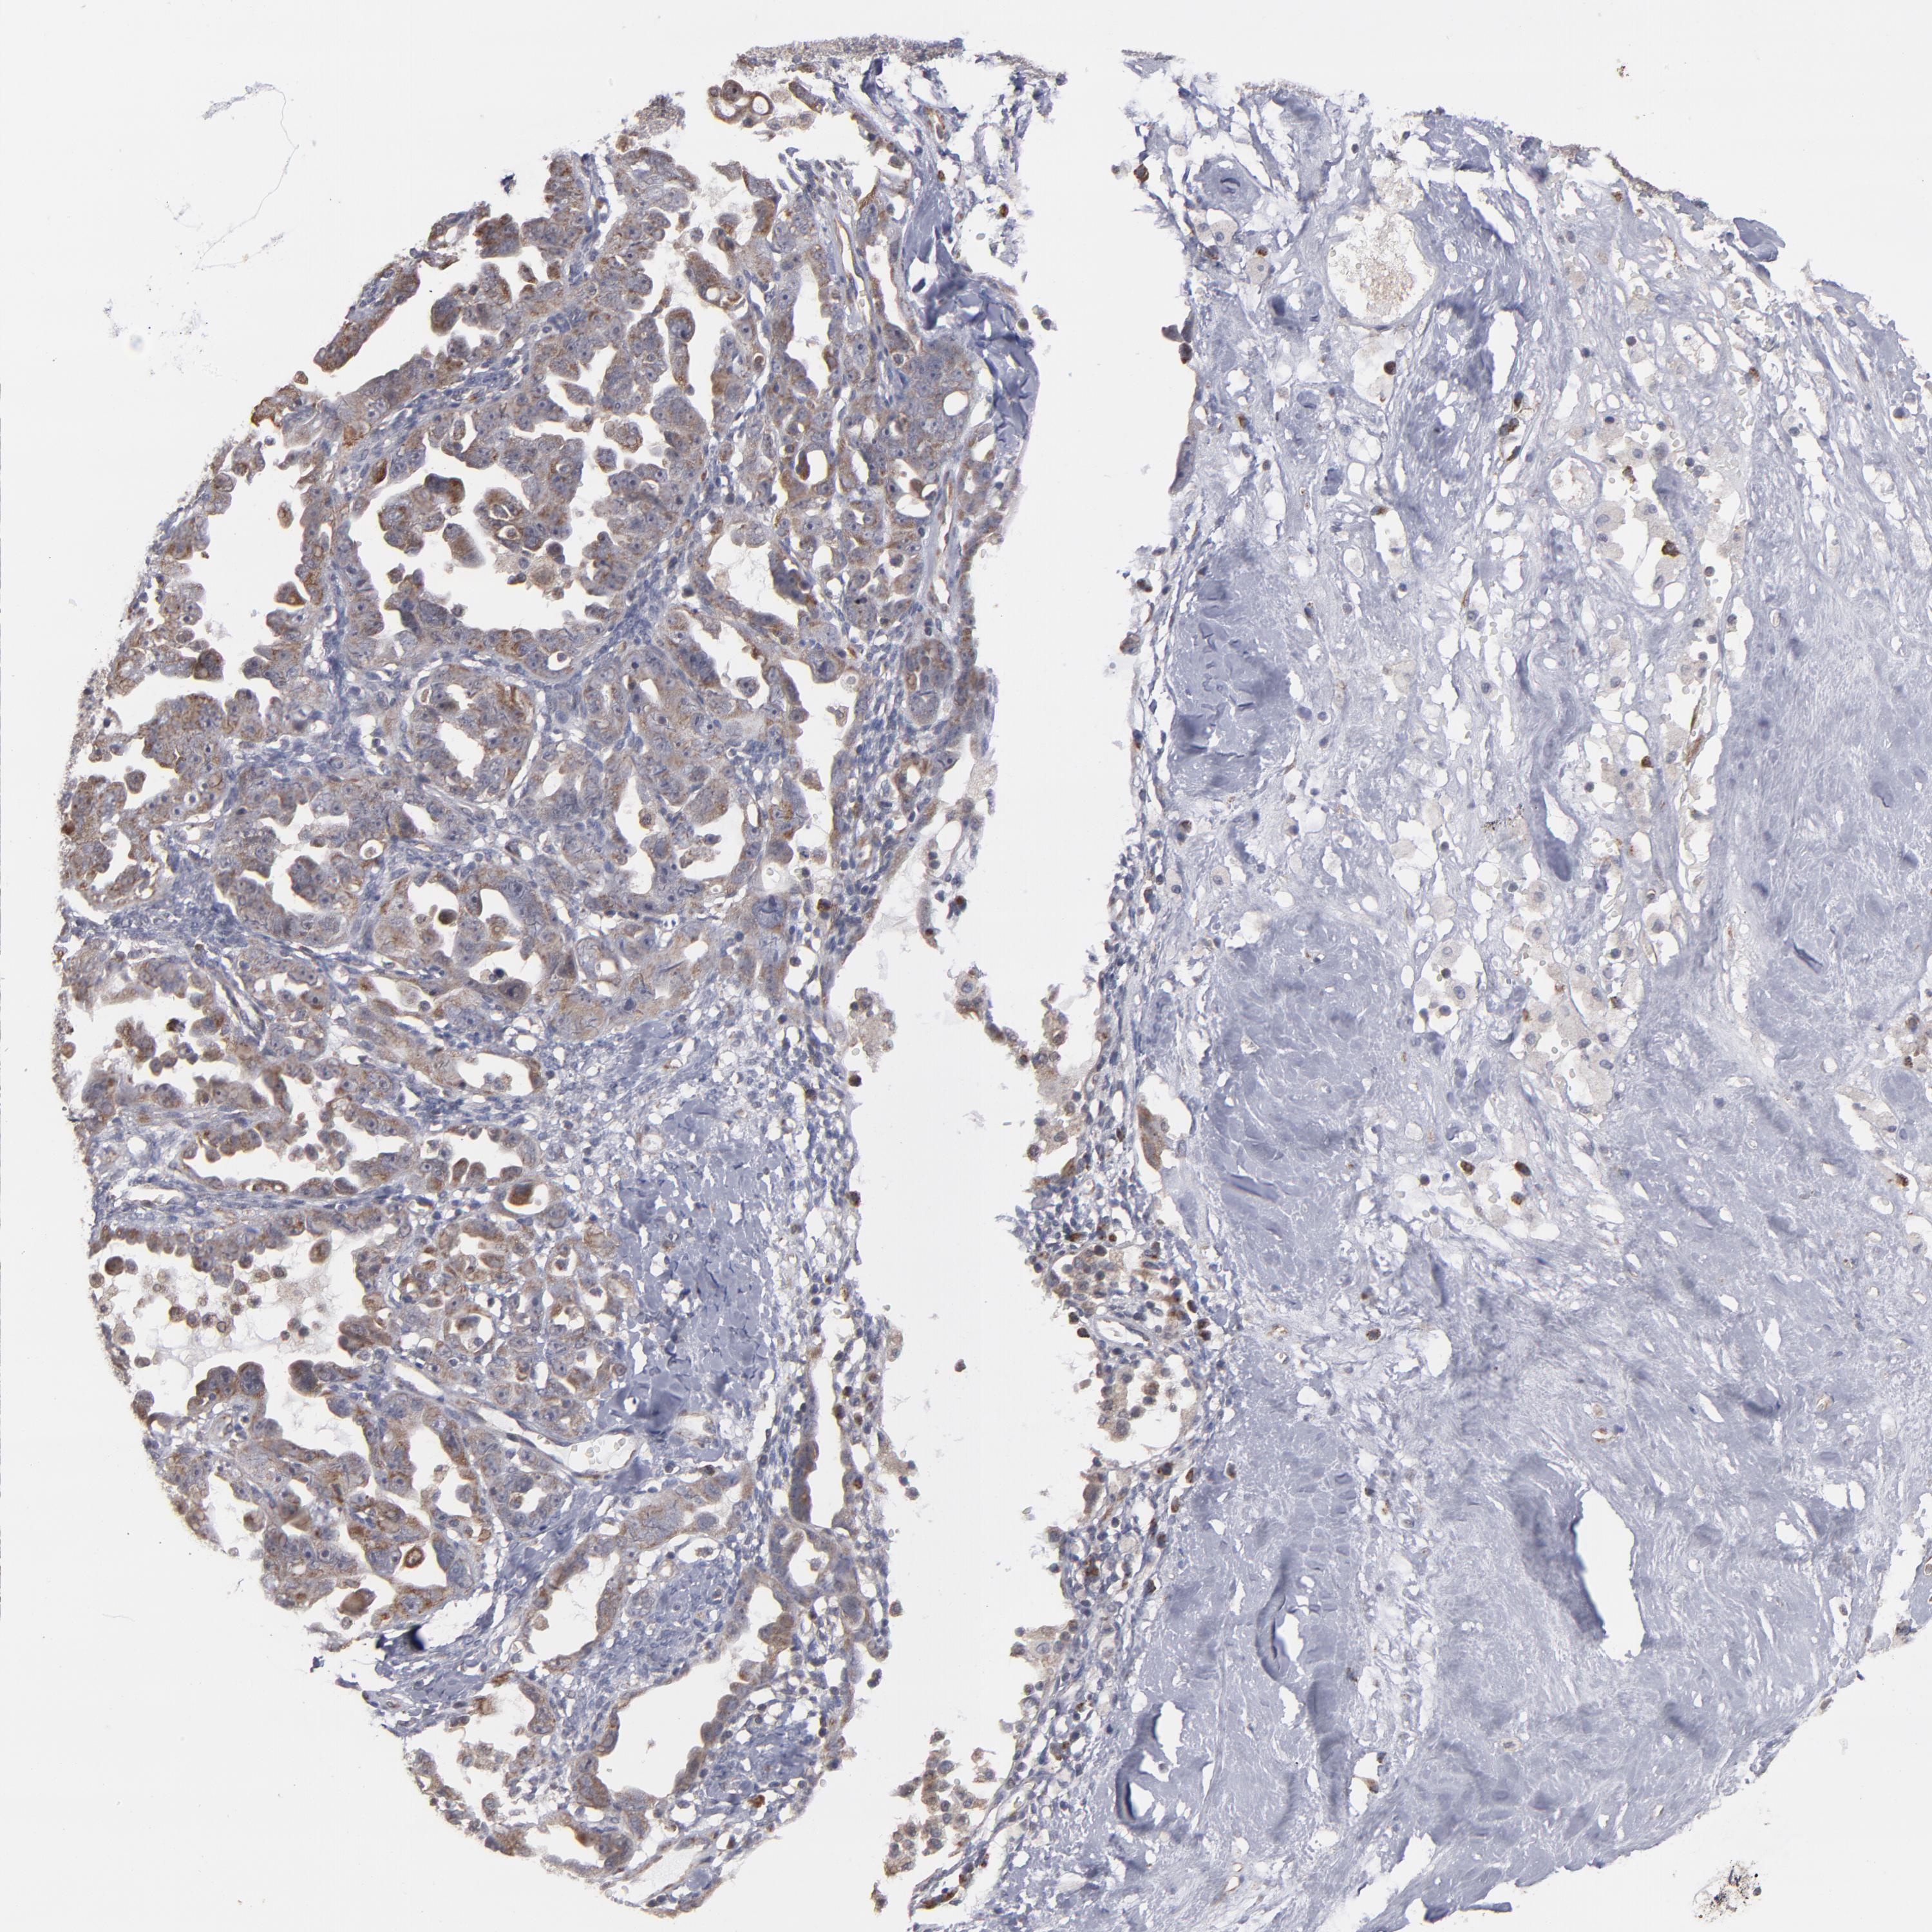

OVARIAN CANCER - Protein expressioni

A mouse-over function shows sample information and annotation data. Click on an image to view it in a full screen mode. Samples can be filtered based on level of antibody staining by selecting one or several of the following categories: high, medium, low and not detected. The assay and annotation is described here.

Note that samples used for immunohistochemistry by the Human Protein Atlas do not correspond to samples in the TCGA dataset.

Antibody stainingi

Antibody staining in the annotated cell types in the current human tissue is reported as not detected, low, medium, or high, based on conventional immunohistochemistry profiling in selected tissues. This score is based on the combination of the staining intensity and fraction of stained cells.

Each image is clickable and will lead to virtual microscopy that enables deeper exploration of all samples and also displays staining intensity scores, fraction scores and subcellular localization as well as patient and tissue information for each sample.

Antibody HPA002893

Staining

High

Medium

Low

Not detected

Intensity

Strong

Moderate

Weak

Negative

Quantity

>75%

75%-25%

<25%

None

Location

Nuclear

Cytoplasmic/membranous

Cytoplasmic/membranous,nuclear

Cystadenocarcinoma, serous, NOS

Cystadenocarcinoma, mucinous, NOS

Carcinoma, endometroid